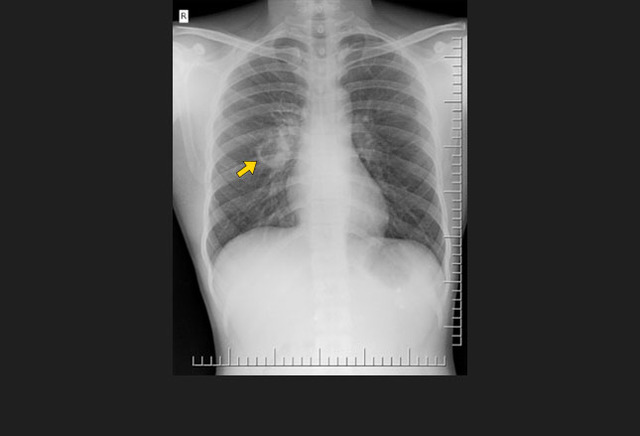

图2. 无数的肺部小结节,与粟粒型肺结核表现一致

初次感染结核常为隐匿性经过,少数患者可能会有明显的血液播散,导致粟粒型肺结核。